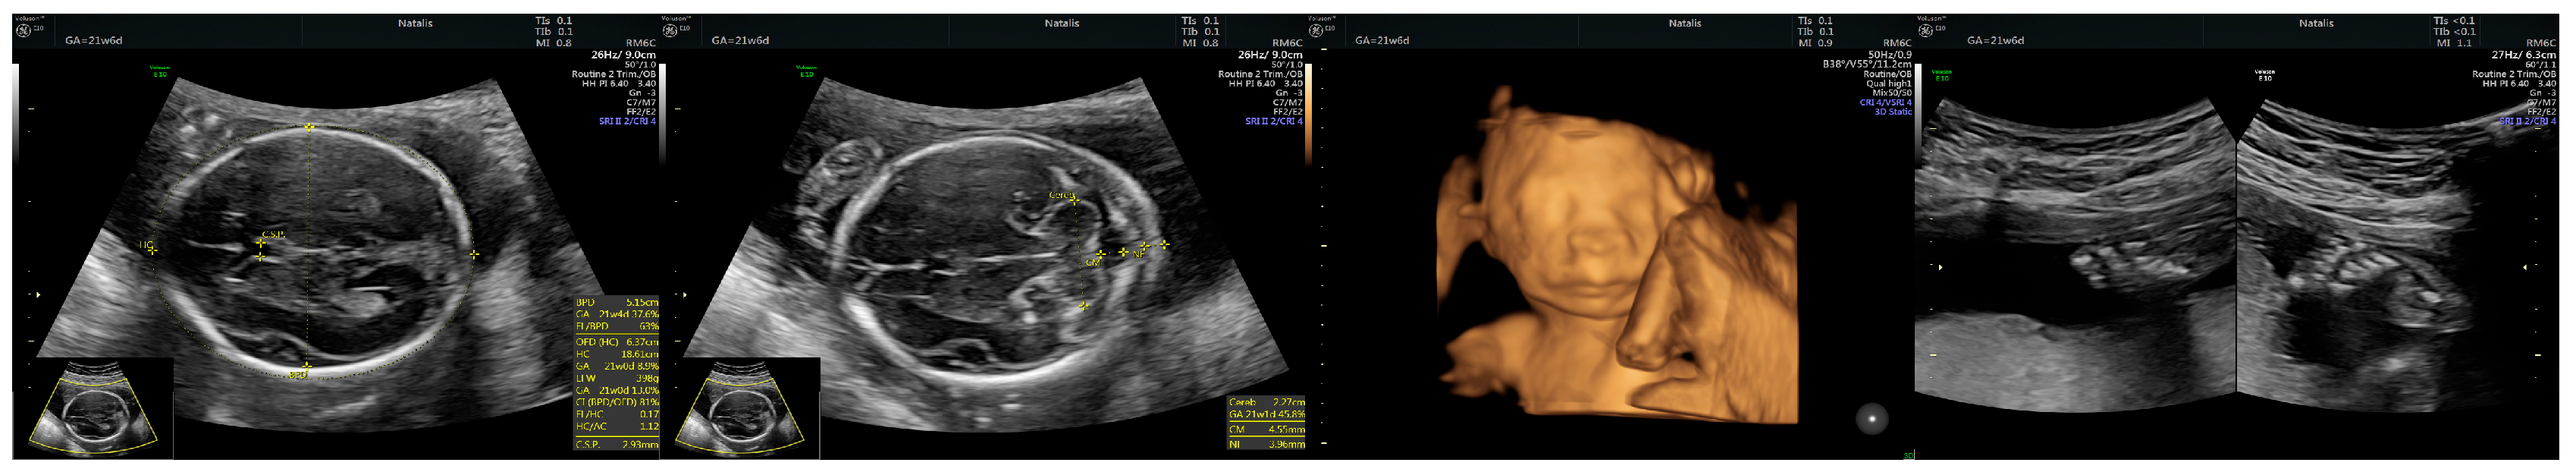

2.1. Case Presentation

2.2. Case Management

| Prenatal Ultrasound Findings | 21 + 6 | 26 + 6 | 28 + 6 | Frequency of Postnatal Findings in the Literature |

| Pointed forehead/premature closure of the metopic suture | - | + | +++ | ? |

| Hypotelorism | - | + | +++ | Rather hypertelorism |

| Micrognathia/small chin size | - | + | +++ | +++ |

| Corpus callosum hypoplasia | - 19.9 mm > 5% (19.54 mm) | + 27.7 mm < 5% (29.91 mm = 5%) | Difficult to visualize—premature metopic suture closure | ++ |

| Broad thumb | - | +++ | +++ | +++ |

| Rocker-bottom feet | - | +++ | +++ | +++ |

| Short femur | - | + | ++ | +++ |